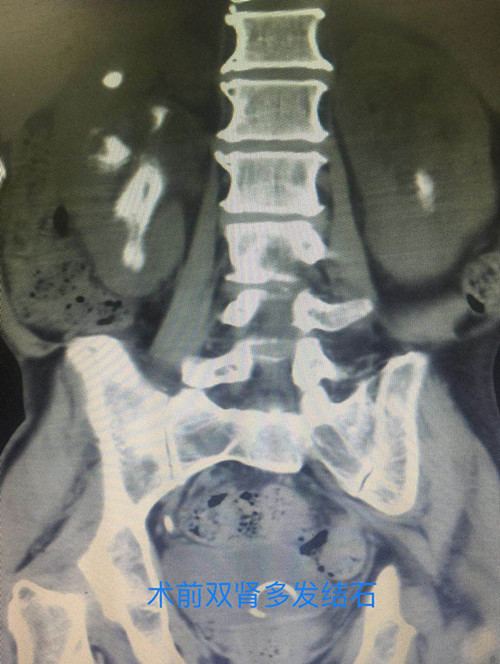

泌尿外科手术效果图